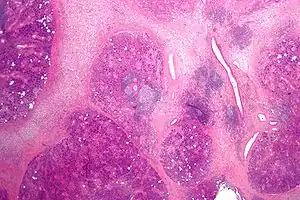

Micrograph of chronic inflammation of the salivary gland sialadenitis)